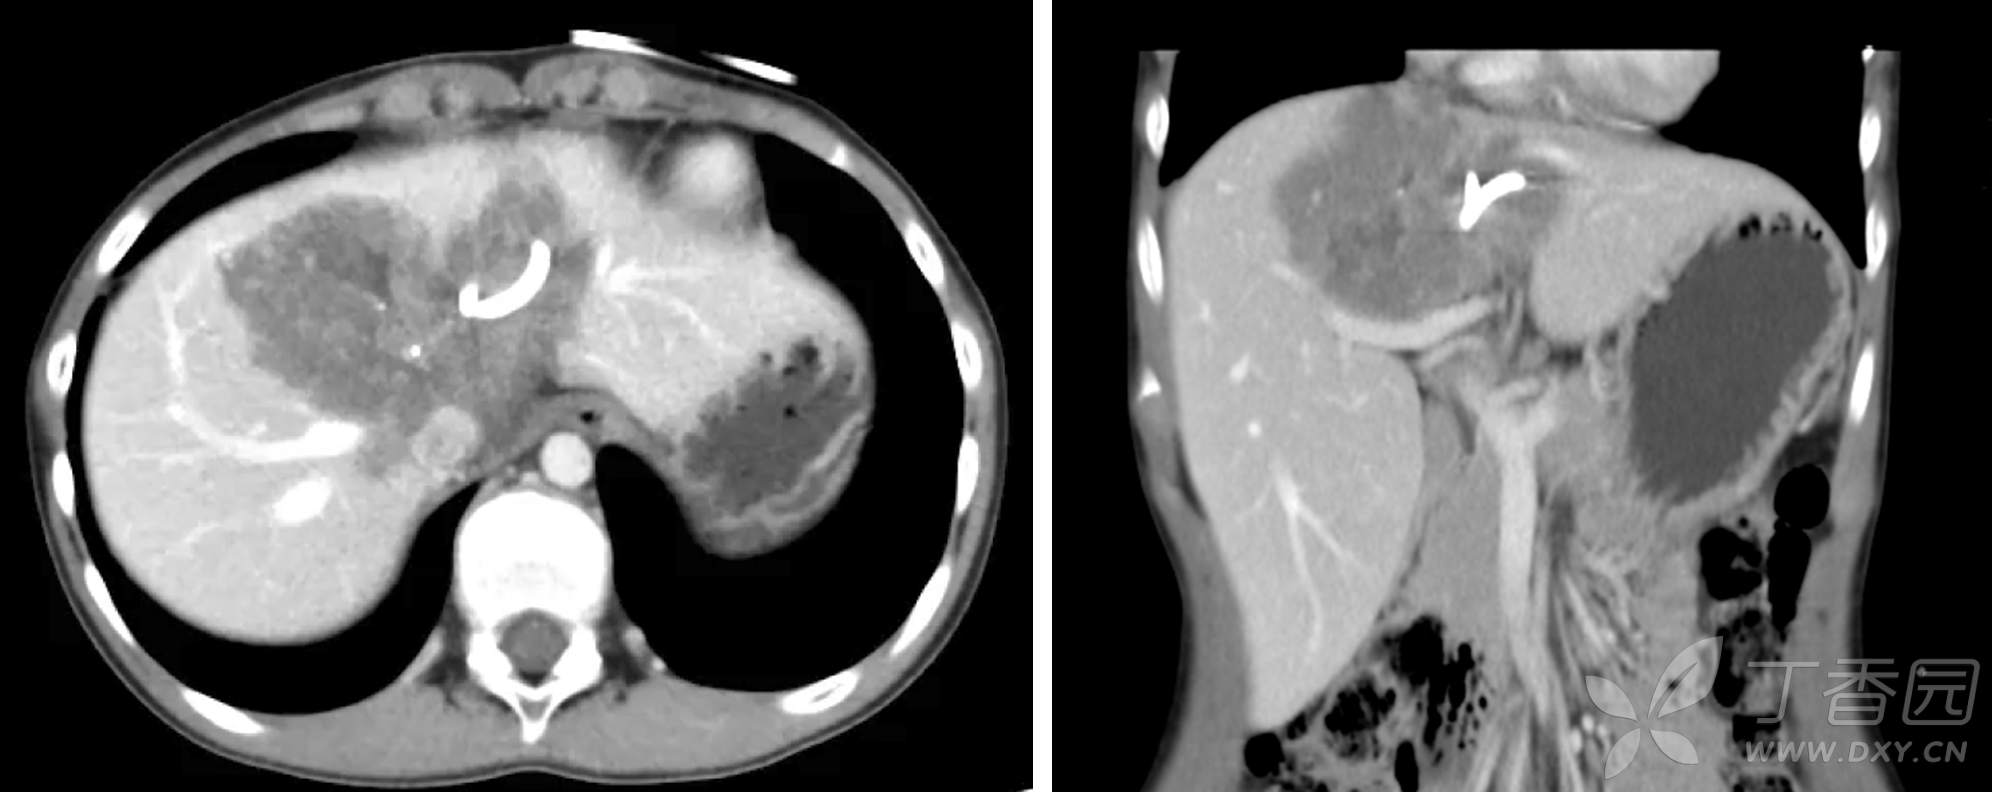

16岁女患者,玉树来的藏胞,因梗阻性黄疸,在当地诊断为左肝泡型肝包虫,左侧PTBD后来院。化验基本正常,影像学检查如下:

此人解剖变异,右前支和左支汇合成共干,左三肝切除变得比较容易。但是泡型肝包虫是良性疾病,不同于恶性肿瘤需要一定的切缘,应该在确保切净的情况下,尽可能多的留下正常的肝脏。所以主刀医生计划从右前肝蒂表面劈开,保留背侧亚支,切除腹侧亚支。如下: